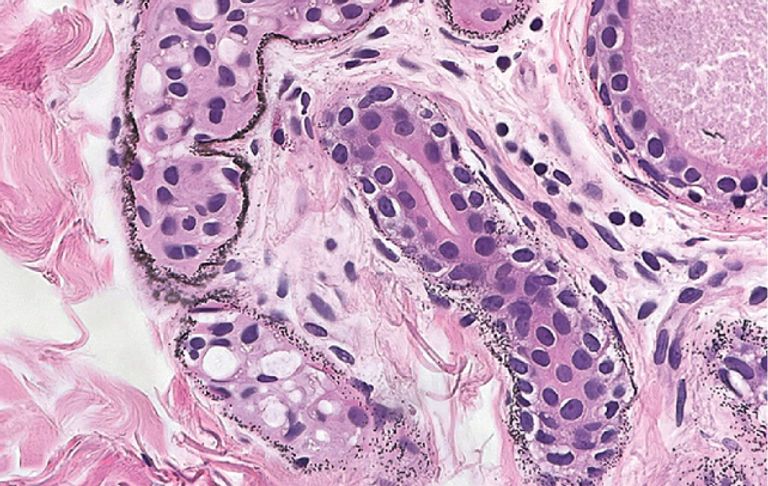

كشفت التحاليل عن وجود تركيز للفضة في جسمه أعلى بـ40 مرة من المستوى الطبيعي، مما أدى إلى تراكم جسيمات صغيرة من المعدن المؤكسد في مناطق مثل غدد العرق والأوعية الدموية وألياف الجلد.

هذه الحالة النادرة تُعرف بـ"الأرجيريا" (Argyria)، وتنتج عن تراكم الفضة في أنسجة الجسم بشكل غير طبيعي.